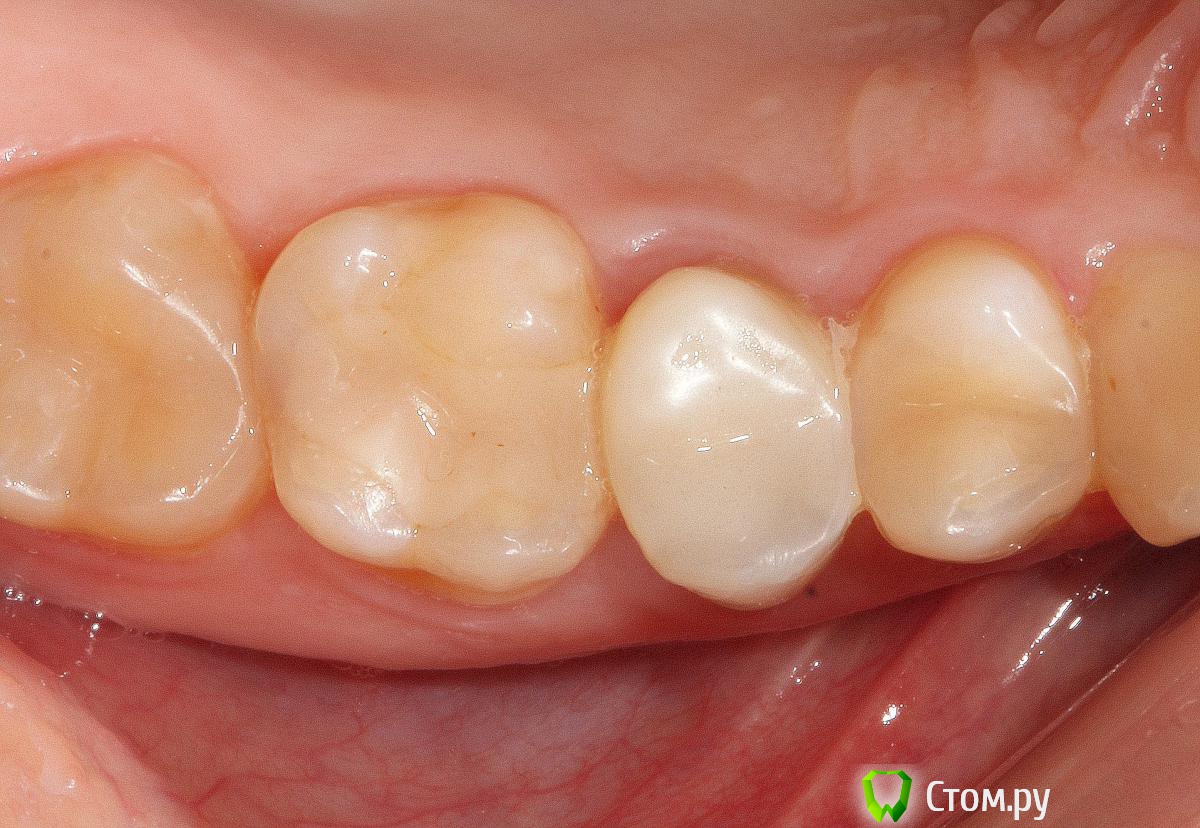

SDC Опубликовано 19 ноября, 2014 Поделиться Опубликовано 19 ноября, 2014 (изменено) Prettau, извините, не знаю, как редактировать название темы. Здравствуйте всем. В хирургическом много практиков, а по протетике - много теории)). Итак, разбавляю вино. (теория вечна)Протезирование премоляров коронками Преттау с нанесением керамики вестибулярно.Много фото, прошу прощения, поэтому без радикала, превью. Наверное даже так лучше, потому, что по клику откроются не сжатые фото, а радикал жмет.Протезирование в течение 2 недель. Фиксация на фуджи, без коффердама, но в сухих условиях (коффер не поставить по причине глубокий дистальной границы препарирования на обоих премолярах - глубокий кариес проксимальных поверхностей в анамнезе)Рг-контроль на предмет остатков цемента и на последнем фото удаленные излишки цемента на перчатке. Изменено 19 ноября, 2014 пользователем SDC 7 Ссылка на комментарий

SDC Опубликовано 20 ноября, 2014 Автор Поделиться Опубликовано 20 ноября, 2014 Отличный результат. Позвольте несколько вопросов.СВШ в боковых не ставите вообще,если да,то по какой причине?Как думаете антагонисты не будут истираться?Вы как-то меняете анатомию контакта при глубоких дефектах и недостатка сосочка?Спасибо.Спасибо Роман.По поводу штифтов. На самом деле, не имеет значения для меня.Важно, что не было титановых во фронтальном отделе (открываются при редукции тв.тк. небольшой объем композита вокруг штифта, что приводит к хрупкости билдапа и иногда металл.штифты светят через композит и керамику)Антагонисты истираться будут, а цирконий - нет. Что поделаешь.Сейчас мы с техником делаем нанесение вестибулярно и по скатам бугров, для уменьшения негативного эффекта повышенной прочности циркония и ускорения сдаваемости.контакт всегда площадочный, пятно контакта в корональной 1/4.Дефицит мягких тканей керамикой никогда не восполняем. Моделировка коронки максимально анатомична. Ссылка на комментарий